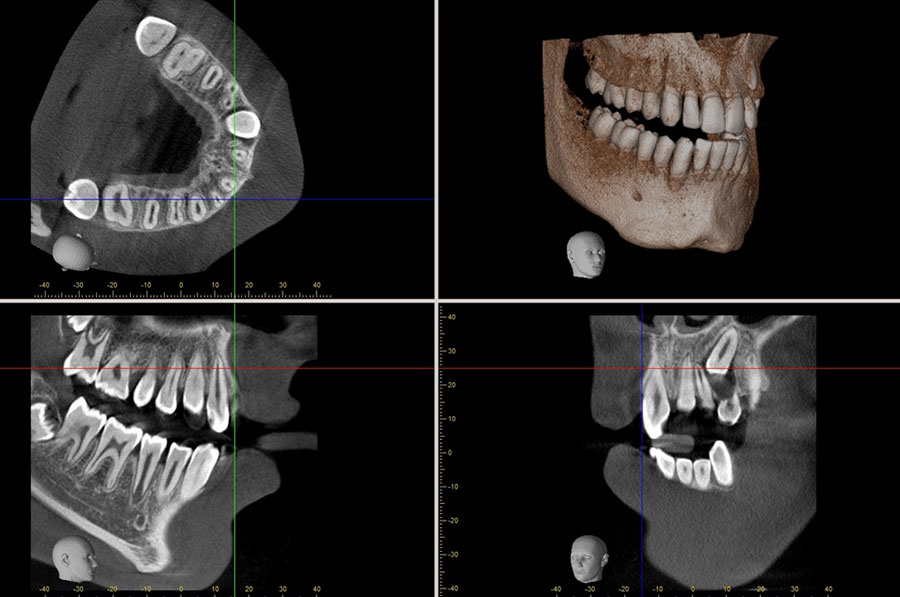

DENTAL TOMOGRAFİ

Dental tomografi, x-ışını kullanılarak incelenmesi gereken bölgenin kesitsel görüntülerini oluşturan bir radyolojik tanı yöntemidir.